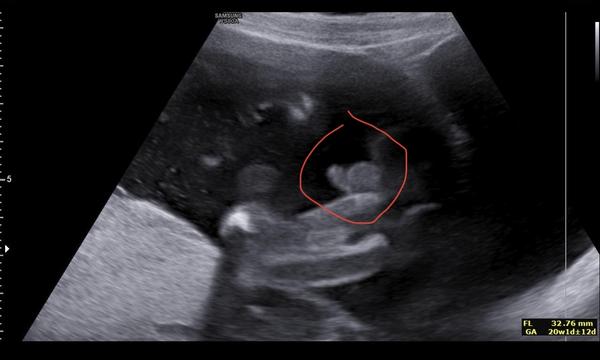

Tak jsme to, holky, moc netrefily, je to kluk😅😅😅

Já to trefila, na začátku diskuze jsem to psala😃😃Já tam prostě toho camprdlíka viděla 😃😃😃❤🌹Moc gratuluji 🌹🌹❤🤰

@gruyerre no...😂 koukej, ještě se s nim takhle vytasil😀

@terezie90 no ano, ty jediná jsi to říkala dobře😀🩷 já taky myslela, že je to celkem jasná holka😀🫣 Děkuju🙂